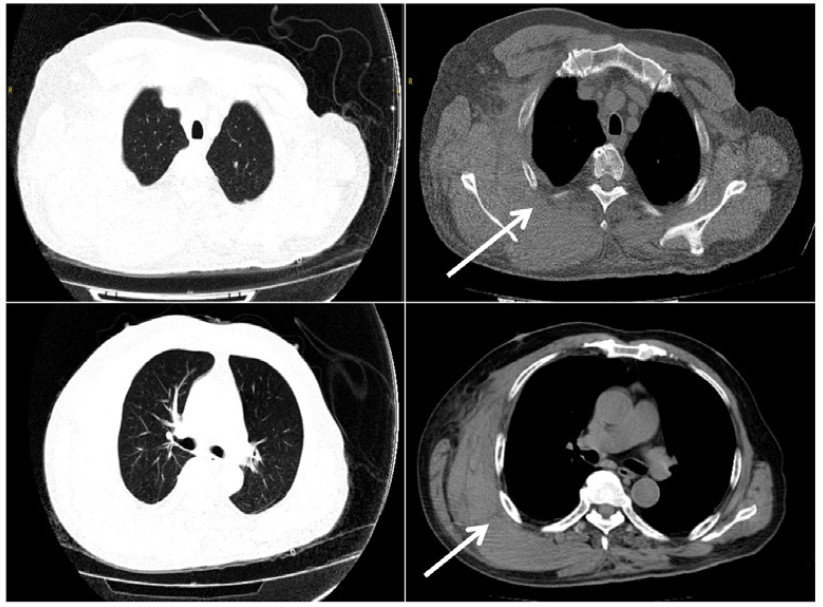

入抢救室后,综合评估出血及再发心梗风险后,暂予以阿司匹林0.1 g qd单抗及对症治疗(图 1)。2024-10-20随访实验室检查示,血常规:血红蛋白68 g/L,血小板计数193×109/L,肌酐107 μmol/L,肌钙蛋白T 0.228 ng/mL。心电图示:窦性心动过速;左心室肥大伴ST-T改变(RV6+SV2=44 mm)。CT示(图 2):右侧胸壁血肿伴少许渗出;右侧胸腔少量积液。请普外科、胸外科、介入科、心内科、血管外科多学科急会诊后,予以停用抗血小板治疗并予以胸带加压治疗。10月21日患者诉右背部肿痛未缓解,右背部皮肤瘀斑进行性扩展至颈部。当日随访血红蛋白下降至57 g/L,患者出现心率增快至110~120次/min,患者右侧背部肿胀较前明显。申请输注红细胞2 U,再次多学科急会诊后,行支气管动脉造影术+肋间动脉造影术+锁骨下动脉造影术+急诊肋间动脉栓塞术。4F猪尾巴插管至右侧锁骨下动脉造影示:右侧甲状颈干、右肩峰、右胸廓内/外动脉及其分支未见造影剂外溢;交换4F Cobra导管插管至双侧支气管动脉造影未见造影剂外溢,插管至右侧5~6肋间动脉造影:远端末梢血管稍紊乱,可见造影剂缓慢外溢,微导管超选插管以少许明胶海绵栓塞,复造影示栓塞良好;插管至其余多支右侧肋间动脉均未见造影剂外溢。

| 注:白色箭头为血肿区域 图 2 胸部增强CTA示右侧胸壁巨大血肿 |